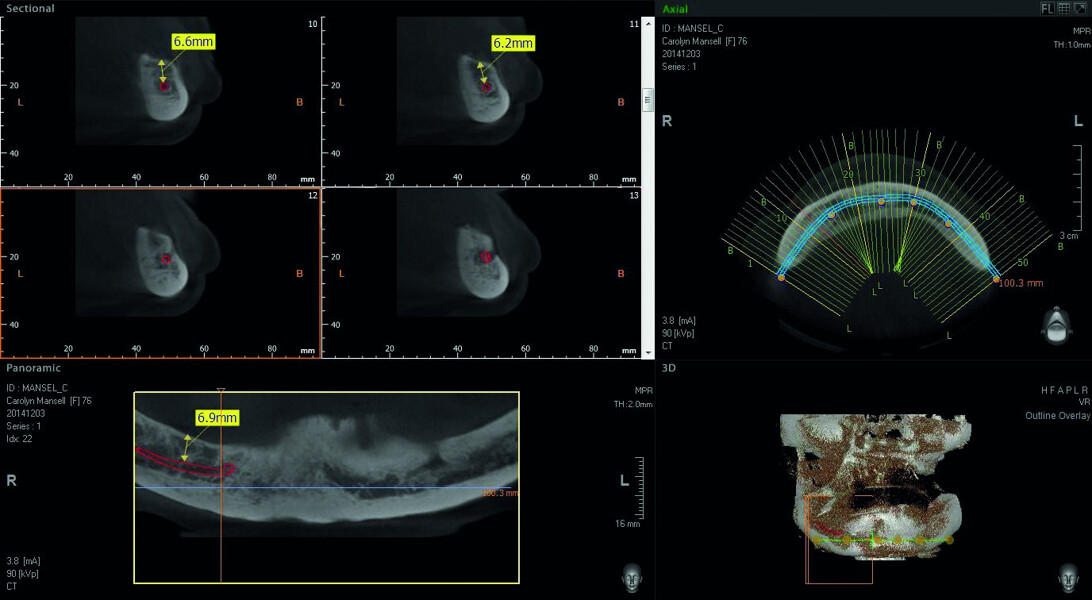

Digitising your implant practice